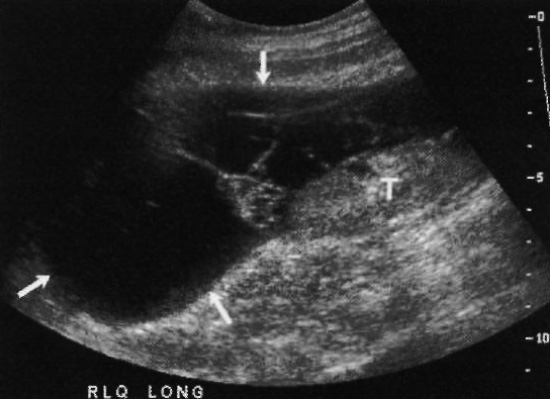

Ультразвуковые признаки абсцесса после трансплантации почки могут быть разными: скопления жидкости с перегородками или детритом (фото 12), плотные образования или полости, в которых содержится газ (фото 13).

Фото 12. Абсцесс трансплантата почки. А – стрелками обозначено скопление со множеством перегородок, локализованное выше мочевого пузыря (BL) по средней линии. УЗИ не позволяет дифференцировать такие образования с лимфоцеле. В – КТ того же пациента: стрелками обозначен абсцесс, который имеет ободок, что позволяет дифференцировать его с лимфоцеле. Указателями обозначены другие абсцессы, которые не удалось обнаружить на УЗИ